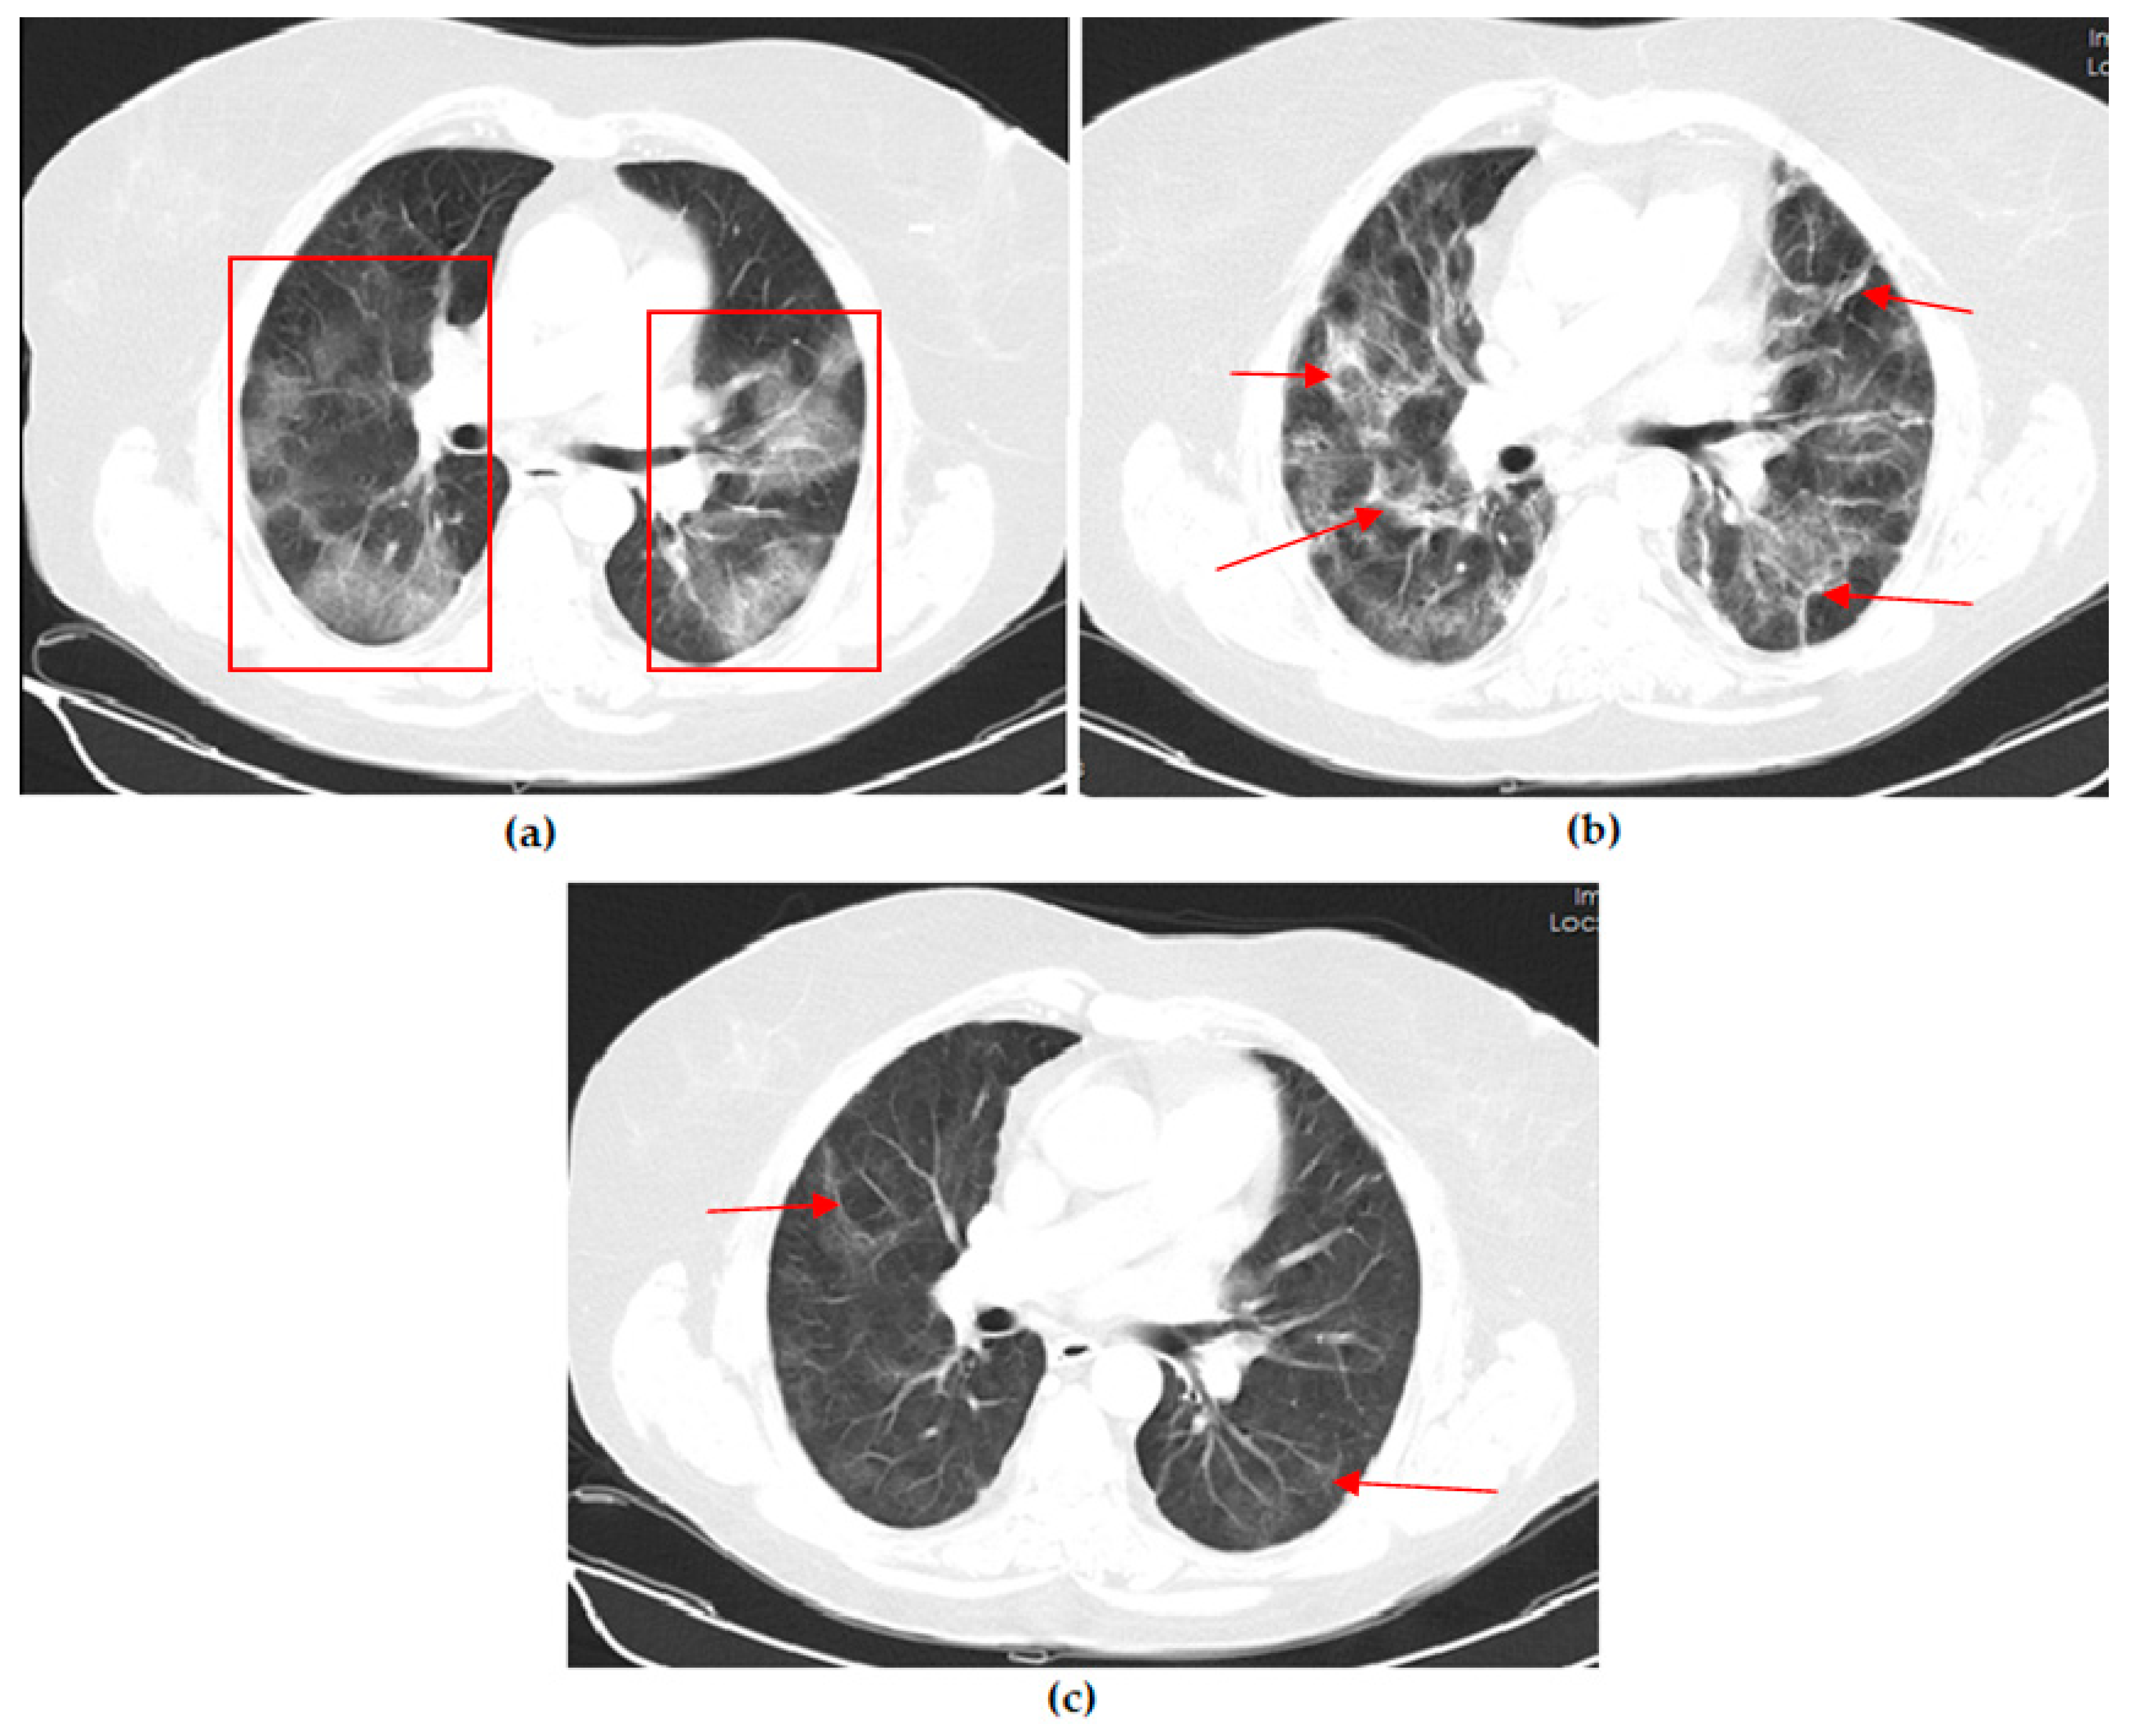

Thoracic CT images of a 51-year-old unvaccinated patient are shown in Figure 1.

Figure 1. A 51-year-old unvaccinated female COVID-19 patient presenting with fever with dry cough for 4 days. (a) The axial thorax CT image shows a diffuse ground glass opacity (GGO) appearance in the bilateral lower lobes and right middle lobe (red frames) and a reversed halo sign (white arrow) in the lateral basal segment of the left lower lobe at presentation. (b) The 1st month, (c) 3rd month, and (d) 6th month follow-up axial thorax CT images show that GGO appearance of the bilateral lower lobes is lesser compared to the previous CT scan. Multiple fibrotic parenchymal bands (red arrows) were found, especially in the anterior basal segment of the right lower lobe.